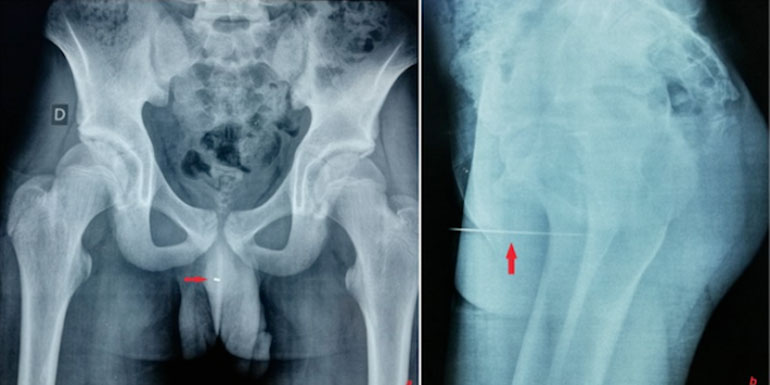

Le faits divers du jour est assez wtf ou un adolescent qui n’arrivait plus à uriner s’est rendu chez le médecin. Honteux, il explique avoir enfoncé une aiguille 9 cm dans l’urètre pour la stimulation érotique que cela lui procurait. Les médecins de l’hôpital tunisien de La Rabta ont publié un papier dans le numéro de juillet de la revue Urology Case Reports, dans lequel ils expliquent qu’is ont retrouvé une aiguille dans le pénis d’un patient. Une tige en métal de 9 cm, logée à 5 cm de profondeur dans l’urètre. Aiguille penis L’adolescent âgé de 14 ans déclare avoir enfoncé l’aiguille pour la sensation érotique que cela lui procurait. Placé sous anesthésie générale, les médecins lui ont retiré l’aiguille de l’urètre au forceps. Heureusement, il n’y a pas eu de complications après l’opération, et notre jeune fétichiste a pu quitter l’hôpital le jour suivant. Il a également passé plusieurs examens psychiatriques, mais aucun trouble mental n’a été diagnostiqué mais par précaution, un suivi psychologique lui a également été imposé. Le sodurètre Aiguille penis L’équipe de l’hôpital de La Rabta déclare que ce n’est pas la première et que cette pratique sexuelle se nomme le sodurètre : "Les objets retrouvés vont des aiguilles aux crayons, stylos, câbles, épingles à nourrice, pailles, cordes, brosses à dents, stérilets, batteries, ampoules, cotons-tiges, verres en plastique, thermomètres aux plantes et légumes, en passant par des membres d’animaux", déclarent-ils. L’insertion peut provoquer des infections Quand les objets ne sont pas stériles, l’insertion peut provoquer des infections et des blessures à l’urètre expliquent les médecins. Un conseil : si l’envie vous prend d’insérer quoique ce soit dans votre urètre, ne le faites pas !